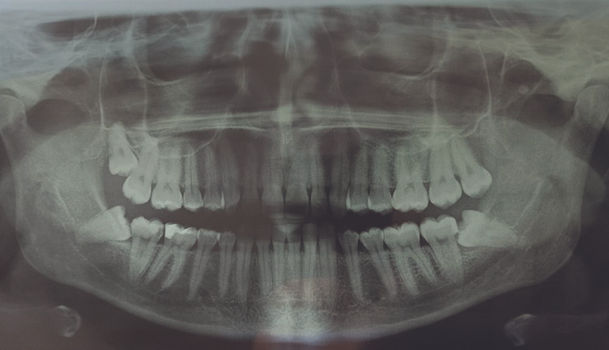

Ретиниран мъдрец е напълно оформен зъб, който е напълно скрит в челюстната кост или не е поникнал напълно, а само фрагмент от коронката му се вижда на повърхността. Това може да причини много неприятни симптоми, включително кариес на съсдения, повтарящ се гингивит или болка в челюстта. Най-често проблемът със задържани/ретинирани зъби засяга мъдреците.

Осемте зъба най-често се появяват на възраст между 17 и 25 години, но те могат да поникнат и на много по-късна възраст или изобщо да не се появят в устата.

На първо място, напреднал кариес. В този случай лечението на канали не винаги е ефективно. Друга индикация за отстраняване на осми зъби са ортодонтските проблеми. Мъдрецът може да причини изтласкване на останалите зъби, което има сериозни последици. Те включват не само криви зъби, но и значително увеличават риска от инфекции и кариеси. Възпалението на венците също е индикация за отстраняването им. Натрупаните бактерии могат да доведат до инфекция на организма.

Неправилното пробиване на мъдрец може да доведе и до увреждане на корените на съседните зъби, което до довете до отстраняването и на двата.